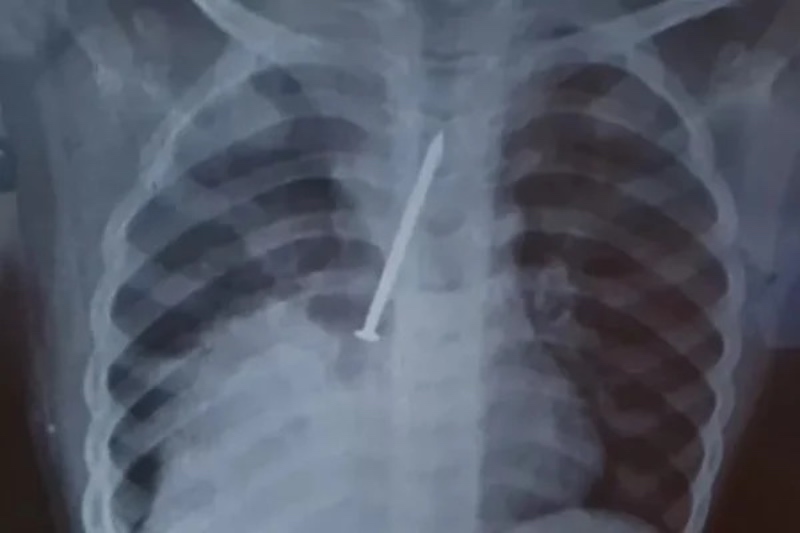

Insatisfeitos, os pais da criança resolveram fazer um exame raio-x particular. Foi quando identificaram a gravidade do problema do filho, que foi transferido para o Hospital Geral do Estado (HGE), onde o garoto passou por uma cirurgia, mas não resistiu.